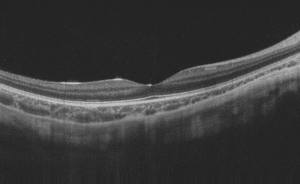

Fundus imaging: right eye color

Fundus imaging: left eye color